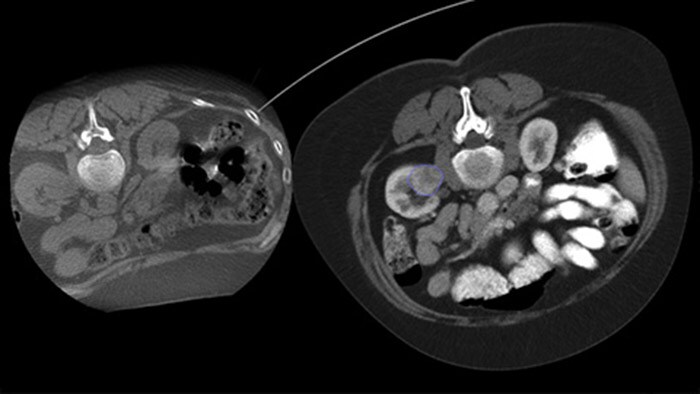

O recurso Dual View permite a sobreposição de uma imagem 3D pré-procedimento (TC/RM/PET-TC) a uma CBCT Dupla 3D intraprocedimento para uma melhor visualização das lesões e acesso a dados cruciais para o planejamento da agulha.

Com a CBCT, você pode adquirir uma CBCT pós-ablação para demonstrar a extensão da cobertura do tumor e confirmar a completude do seu tratamento.